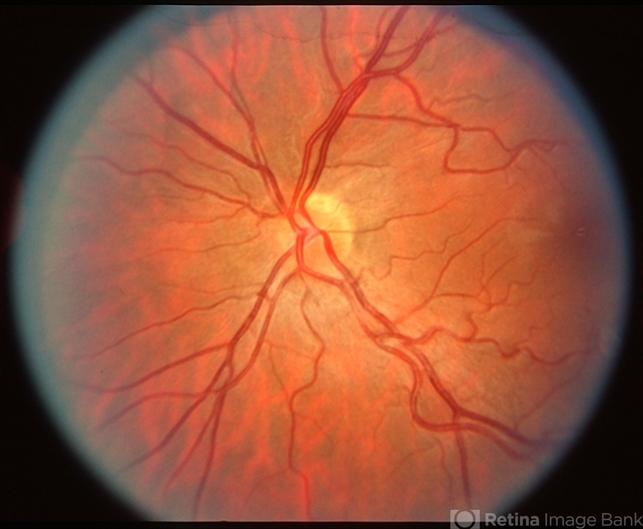

- disc hypoplasia, tilted disc

- Disc hypoplasia; tilted disc and field defect.